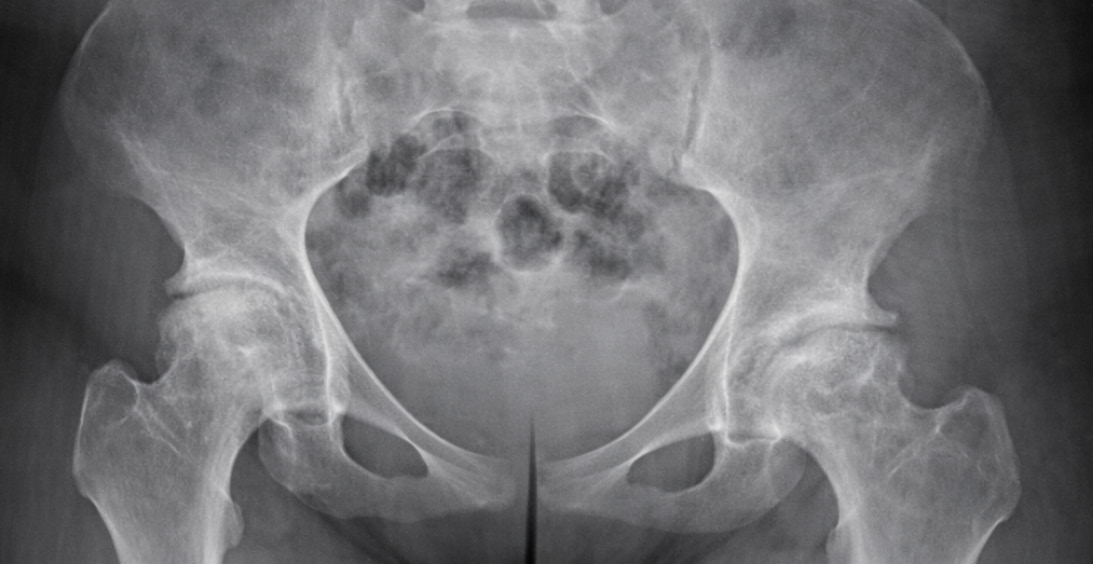

From the Guest Nation: Patients with sickle cell disease pose challenges for total hip arthroplasty

Sickle cell disease (SCD) is an inherited hemoglobinopathy characterized by a structural abnormality of hemoglobin that results in significant systemic and musculoskeletal complications.